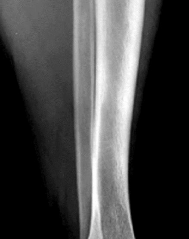

Question 13:

Articular cartilage relies on a highly organized extracellular matrix for its biomechanical properties. In which specific histologic zone of normal hyaline articular cartilage are the collagen fibers oriented primarily perpendicular to the articular surface, and the chondrocytes arranged in distinct vertical columns?

Correct Answer: Deep (radial) zone

Explanation:

Articular cartilage is divided into four main zones. In the superficial (tangential) zone, collagen fibers are parallel to the joint surface to resist shear forces. In the middle (transitional) zone, collagen fibers are randomly oriented. In the deep (radial) zone, collagen fibers are oriented perpendicular to the joint surface and chondrocytes are arranged in vertical columns, providing high resistance to compressive forces. The tidemark separates the deep zone from the calcified zone.